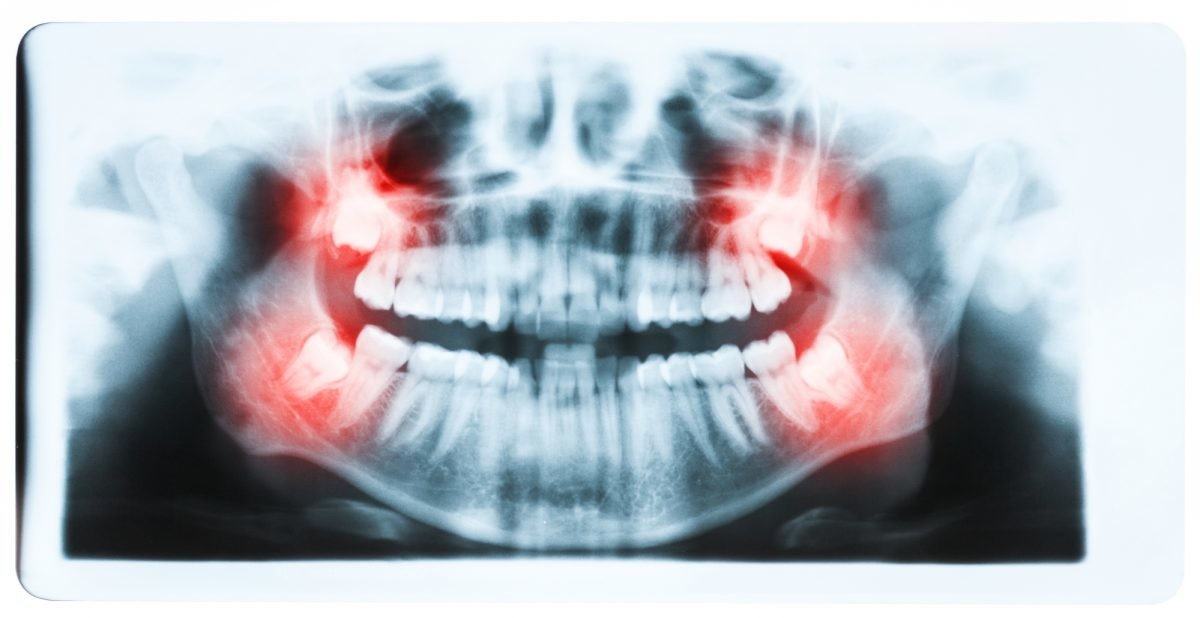

While wisdom teeth may not necessarily cause a major issue with the dental progress that has been made with braces, there may still be reasons to have a wisdom tooth extraction. There are many wisdom tooth concerns that may call for tooth removal surgery, including: Crowding of back teeth, Infected gums, Bone defects, Root resorption, Dental diseases.

If a wisdom tooth becomes impacted or doesn’t erupt straight up, this can cause significant problems for the person. While some people may experience absolutely no problems with their wisdom teeth or get lucky enough to not have any of these extra molars at all, others may experience problems with them.

Fortunately, impacted tooth removal is a common procedure and can provide relief from any pain and discomfort caused by these teeth. In fact, wisdom teeth removal is more common than dental implant procedures, which about three million people have every year.